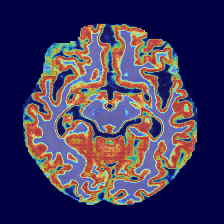

Figure 4: Qualitative comparison of segmentation results on the OASIS-1 and MRBrainS13 datasets. Our proposed PCMambaNet (last column in each set) demonstrates superior performance in boundary delineation and structural coherence compared to several strong baselines. Note our model’s ability to produce segmentations that more faithfully match the ground truth (GT), with noticeably fewer false positives and more accurate handling of complex anatomical regions. Red arrows highlight areas where the advantages of our method are particularly evident.

Qualitative Results. Qualitative results, presented in Figure 4, visually corroborate the quantitative findings and highlight the architectural advantages of PCMambaNet. In the full-data regime (left panel), baseline models often struggle with fine boundaries, producing noisy or incomplete segmentations. In contrast, our model leverages the PPM to focus on critical locations, which then allows the CRN to accurately delineate complex contours that are highly consistent with the ground truth. The superiority of our approach is particularly evident in data-limited conditions (right panel). While competing models yield overly smooth results that miss fine-grained, infiltrative details, our model’s “predict-then-correct” strategy enables it to effectively capture these complex boundary features. Consequently, PCMambaNet produces visually sharper and more anatomically plausible segmentation results, especially in challenging, low-data scenarios.